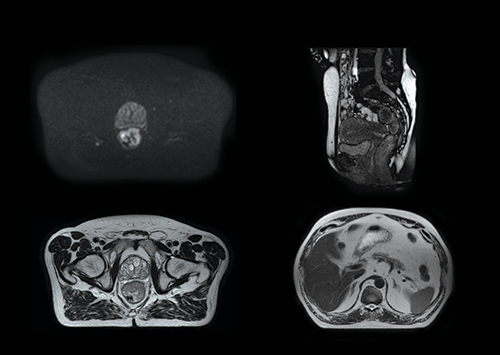

Elekta Unityは,治療ビーム照射前及び照射中に高画質の1.5テスラMRI画像を取得し,腫瘍にのみ高線量を集中できる最初の放射線治療装置です。照射直前にその日の腫瘍と周辺の重要臓器の位置や形状を確認し,必要に応じて治療計画を修正することができます。

(1)治療座標系にキャリブレーションされた高磁場MRIユニットを内蔵しているため,腫瘍と重要臓器を明瞭に識別し,治療計画を立てられます。照射マージンを最小化することで,健常組織への影響を抑えながら,腫瘍への線量を増大できます。

(3)照射開始から終了までリアルタイムで腫瘍や重要臓器の位置・形状の変化を監視できます。コーンビームCTと異なり,イメージガイドのための被曝がありません。例えば,小腸が照射野内に移動した場合に,照射を一時中断することも可能です。